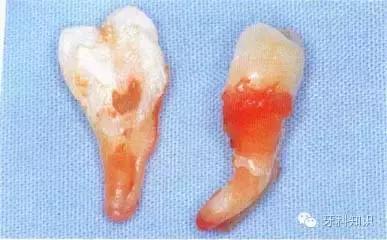

单根牙牙根呈锥形者

,可以稍加旋转力量拔出。

单根牙牙根呈扁平状者(如

)和多根牙,应避免旋转力,并宜顺着牙根弯曲的方向拔出,否则易折断牙根。